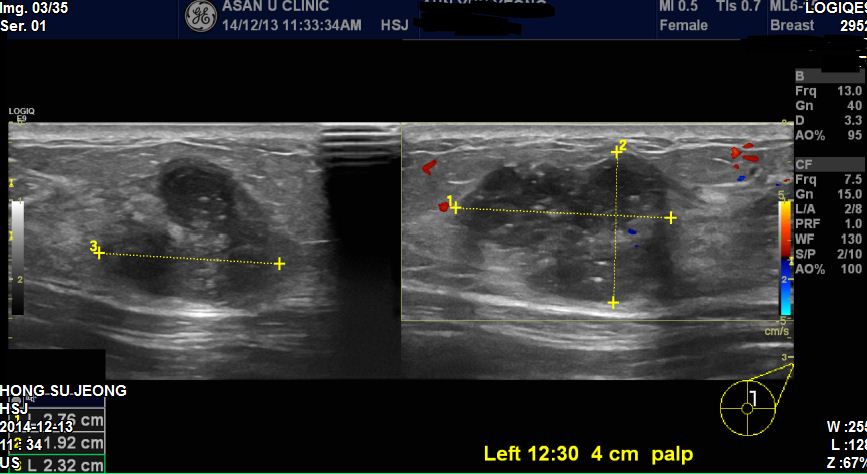

좌측유방에 만져지는 혹이있어 내원하신 30세 여자환자분이십니다

본원에서 초음파 시행 후 좌측유방 12 : 30 방향에 2.7cm 혹과

우측유방에 9 : 00방향에 혹을 조직검사 하였습니다

결과 좌측유방은 침윤성유방암으로 진단되었고 우측은 다행히도

섬유선종으로 진단되었습니다.